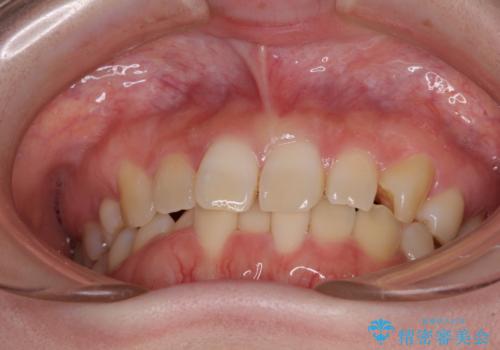

ディープバイトをインビザライン矯正で改善

- 前歯のデコボコと強い咬みしめを気にして来院された患者様です。

インビザラインを用いて、前歯の叢生を解消するとともに、ディープバイトを改善していくこととしました。